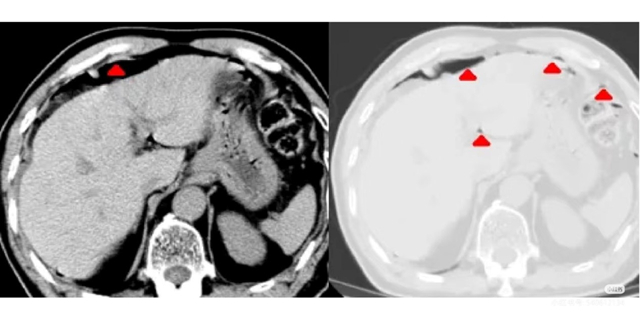

12月3日,66岁的马先生因腹痛到院就诊,急诊行全腹CT平扫检查。放射科徐柱荣副主任医师在阅片时敏锐发现,患者双侧膈下、胆囊窝、肝脾外缘旁、肝肾隐窝及盆腔等部位,均可见弧形、点状、短条状气体密度影,胃肠道内伴有少量液平面,当即确诊为胃肠穿孔并全腹腹水。考虑到病情凶险,需及时准确的诊断以指导后续治疗,放射科第一时间报危机值给主管医生,为临床诊断患者病情提供了重要的诊疗依据。

术后随访的病理结果显示,患者胃窦部前壁存在溃疡,有一个0.5cm×0.5cm的穿孔,穿孔处有胃内容物活动性溢出,量约150ml,部分胃壁与局部大网膜、肠管粘连,且局部组织披附白色脓苔,与放射科术前诊断完全吻合。